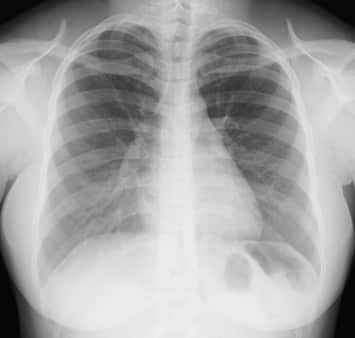

Le cancer du poumon est la cause la plus fréquente de décès par cancer chez les hommes, et est responsable chaque année du décès de 22 000 hommes et 6 500 femmes en France.